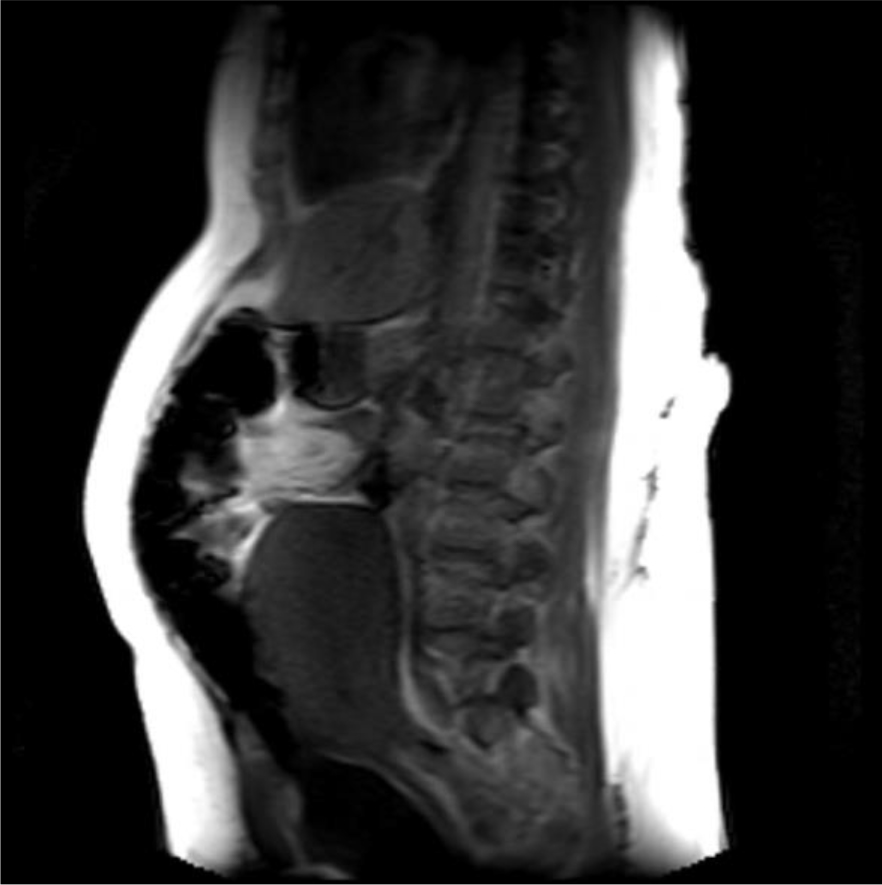

A magnetic resonance imaging (MRI) image of the uterus was given in two cases as an example of the groups that did not apply sandbags (Fig. 2) and that did (Fig. 3).

Fig. 3.Postoperative 4th hour MRI image of a case with sandbag application. It is observed that the anteflexio position of the uterus is impaired.

In our study, as a second theory, we thought that by applying external pressure to the uterus, bleeding after CS could be reduced. Namely, uterine massage [35] aiming to provide contraction of the uterus with fundus pressure, uterine balloon tamponade methods aiming to stop bleeding by applying internal pressure to the uterus [36, 37], uterine compression sutures that are reported to provide hemostasis with 90% success by shrinking the uterine cavity as in bimanual uterine compression (B-Lynch, Hayman, Pereira, Square suture, U sutures, Matsubara, etc.) [38]. Some of the above-mentioned methods are effective in reducing postpartum uterine bleeding by applying pressure to the uterus from the inside, some from the outside and shrinking the uterine cavity. Based on this pressure effect, we investigated its effectiveness as a method for reducing the amount of bleeding after CS by applying abdominal fundal pressure to the uterus in the first 6 hours postpartum. As a result of our study, the amount of bleeding was statistically significantly higher than in our control group. However, when we evaluated it clinically, there was no difference in terms of anemia. In our opinion, the sandbag left on the uterine fundus disrupted the anteflexion position of the uterus and brought it to the extension position. We obtained information about the position of the uterus by magnetic resonance imaging (MRI) in some of our patients who had and did not apply sandbags. As a result of MRI, we observed that the uterus lengthened towards the umbilicus and the anteflexion position was impaired, as if the uterus was in atony in the weight-applied group. According to the results of our study, sandbag application does not seem to reduce bleeding after CS. However, sandbag application may be beneficial in preventing complications such as incision bleeding, hematomas or rectus hematoma formation due to the local pressure effect on the skin and subcutaneous tissues. However, in our study cutaneous, subcutaneous or rectus hematoma was not observed in any of our patients in either group we could not comment on this issue.

In cases where we did not apply weight, we experienced that the uterus contracted like a fist. Our MRI findings showed that weight application could not have a positive effect on uterine contractions contrary to our previous thought. This position disorder and continuous pressure effect in the uterus disrupted the synchronization of uterine contractions and was not effective in reducing bleeding. Because if we think like the B-Lynch effect, while the anteflexion position of the uterus reduces bleeding, we have disrupted this position with a sandbag. Disruption of the postpartum position of the uterus may have caused dysfunction in the contraction of the spiral arteries by the myometrium by disrupting the contraction pattern of the myometrium, or it may have created a trauma effect [23, 24]. In addition, the sandbag may have caused myometrial muscle fatigue by encouraging continuous contraction of the myometrium due to uterine pressure. Zhao et al. [39] used a multifunctional airbag abdominal compression belt in the second and third stages of labor in a study. As a result of the study, the internal pressure of the belt was closely monitored and appropriately adjusted to the patient. It has been reported that the multifunctional airbag abdominal compression belt can accelerate the second and third stages of labor, prevent postpartum hemorrhage and promote natural birth. The sandbag we used in our study can look like to the multifunctional airbag abdominal pressure belt. Because the purpose of both is to apply pressure to the uterine fundus. However, the multifunctional airbag abdominal compression belt has been used to facilitate childbirth. Pressure adjustment control has also been made in this belt. Pressure setting control can be very important during labor. Because there is a fetus that may be at risk. This pressure setting can also be lowered if the fetus is in distress during delivery. However, in our sandbag application, there is no controlled pressure setting, it presses the fundus as much as the weight of the sandbag. However, since we apply the sandbag after birth, we will not have a problem such as fetal distress. As a result, it is similar to our study that the described belt application has been shown to reduce the amount of postpartum hemorrhage as well as facilitating childbirth. However, we showed that sandbag application did not reduce the amount of postpartum bleeding. The reason for this difference may be due to the fact that the belt is more applicable and pressure-adjusted and was applied during delivery. In addition, sandbag application can be considered as a primitive method. However, our sandbag application can apply uterine pressure from the abdomen in non-invasive ways and can give an idea about the construction of pressure-adjusted compressor devices.